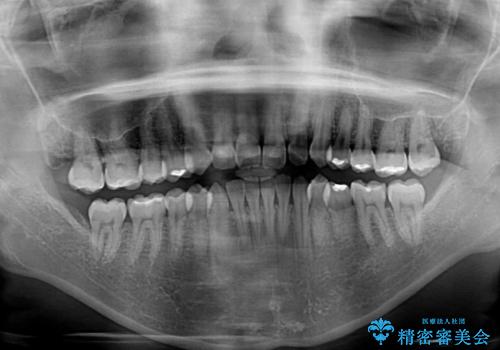

- 上下の前歯のデコボコと奥歯の反対咬合を気にして来院された患者様です。

インビザラインを用い、上下顎ともにIPR(歯と歯の間を削る)により叢生を改善することとしました。

奥歯の反対咬合は、骨格に由来するものであるため、改善できるところまで改善していくこととしました。

治療を長期化させたくないとのご要望があったので、左下の90度捻転した歯は、捻転した状態のゴールとしました。

反対咬合を改善したことで、歯ぎしりしたときの引っかかる感じがなくなり、奥歯への負担を大きく軽減することができました。